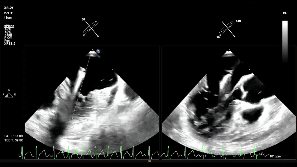

手术过程

患者麻醉后取平卧位,经食管超声(TEE)探头置入到位。股静脉穿刺点消毒铺巾后进行穿刺,并置入鞘管建立工作路径。置入超声引导专用导丝(Panna Wire)和房间隔穿刺针。Panna Wire梭形头端在超声下具有优异的可视性与指向性,将其置入穿刺针内,可实时指导穿刺针的位置。在TEE实时引导下,完成房间隔穿刺。因左心房容积偏小,操作空间受限,故穿刺点选择略靠后,但操作过程顺利,未损伤左心房后壁。

术中影像

房间隔穿刺

置入瓣膜夹

第一次关闭瓣膜夹

超声提示仍存在少量反流